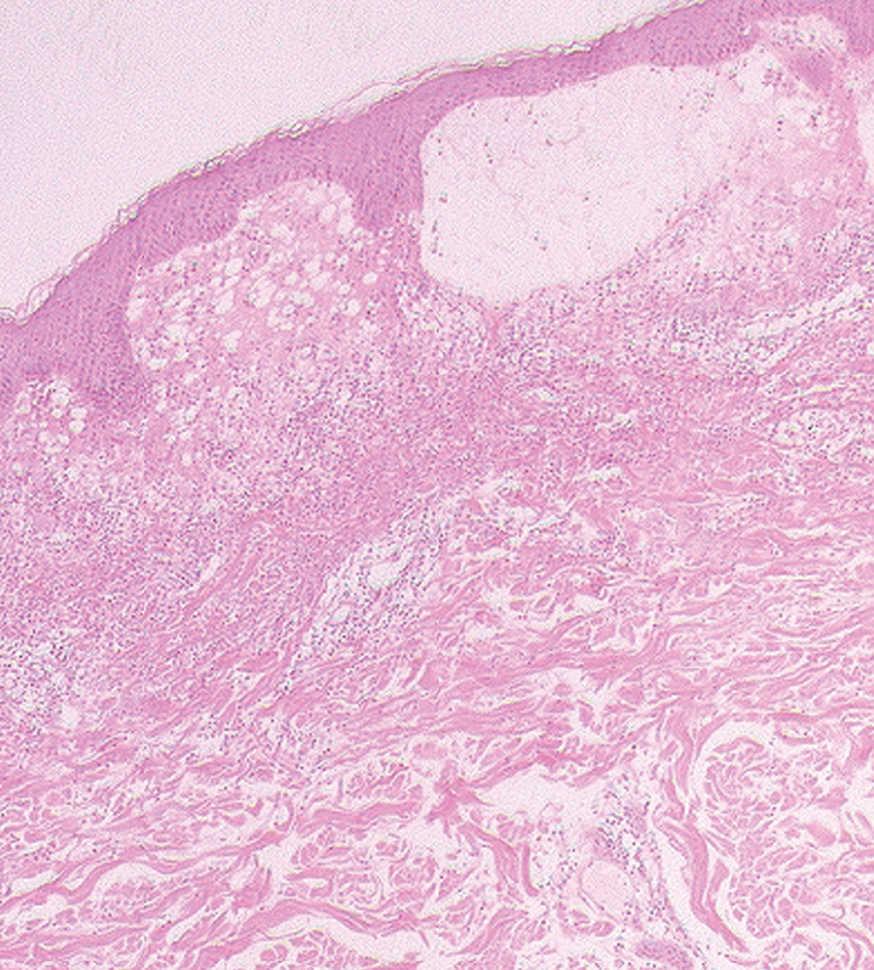

Fig. 3.--Intenso infiltrado dérmico neutrofílico y formación de una ampolla subepidérmica a consecuencia del fuerte edema. (Hematoxilina-eosina, x20.)